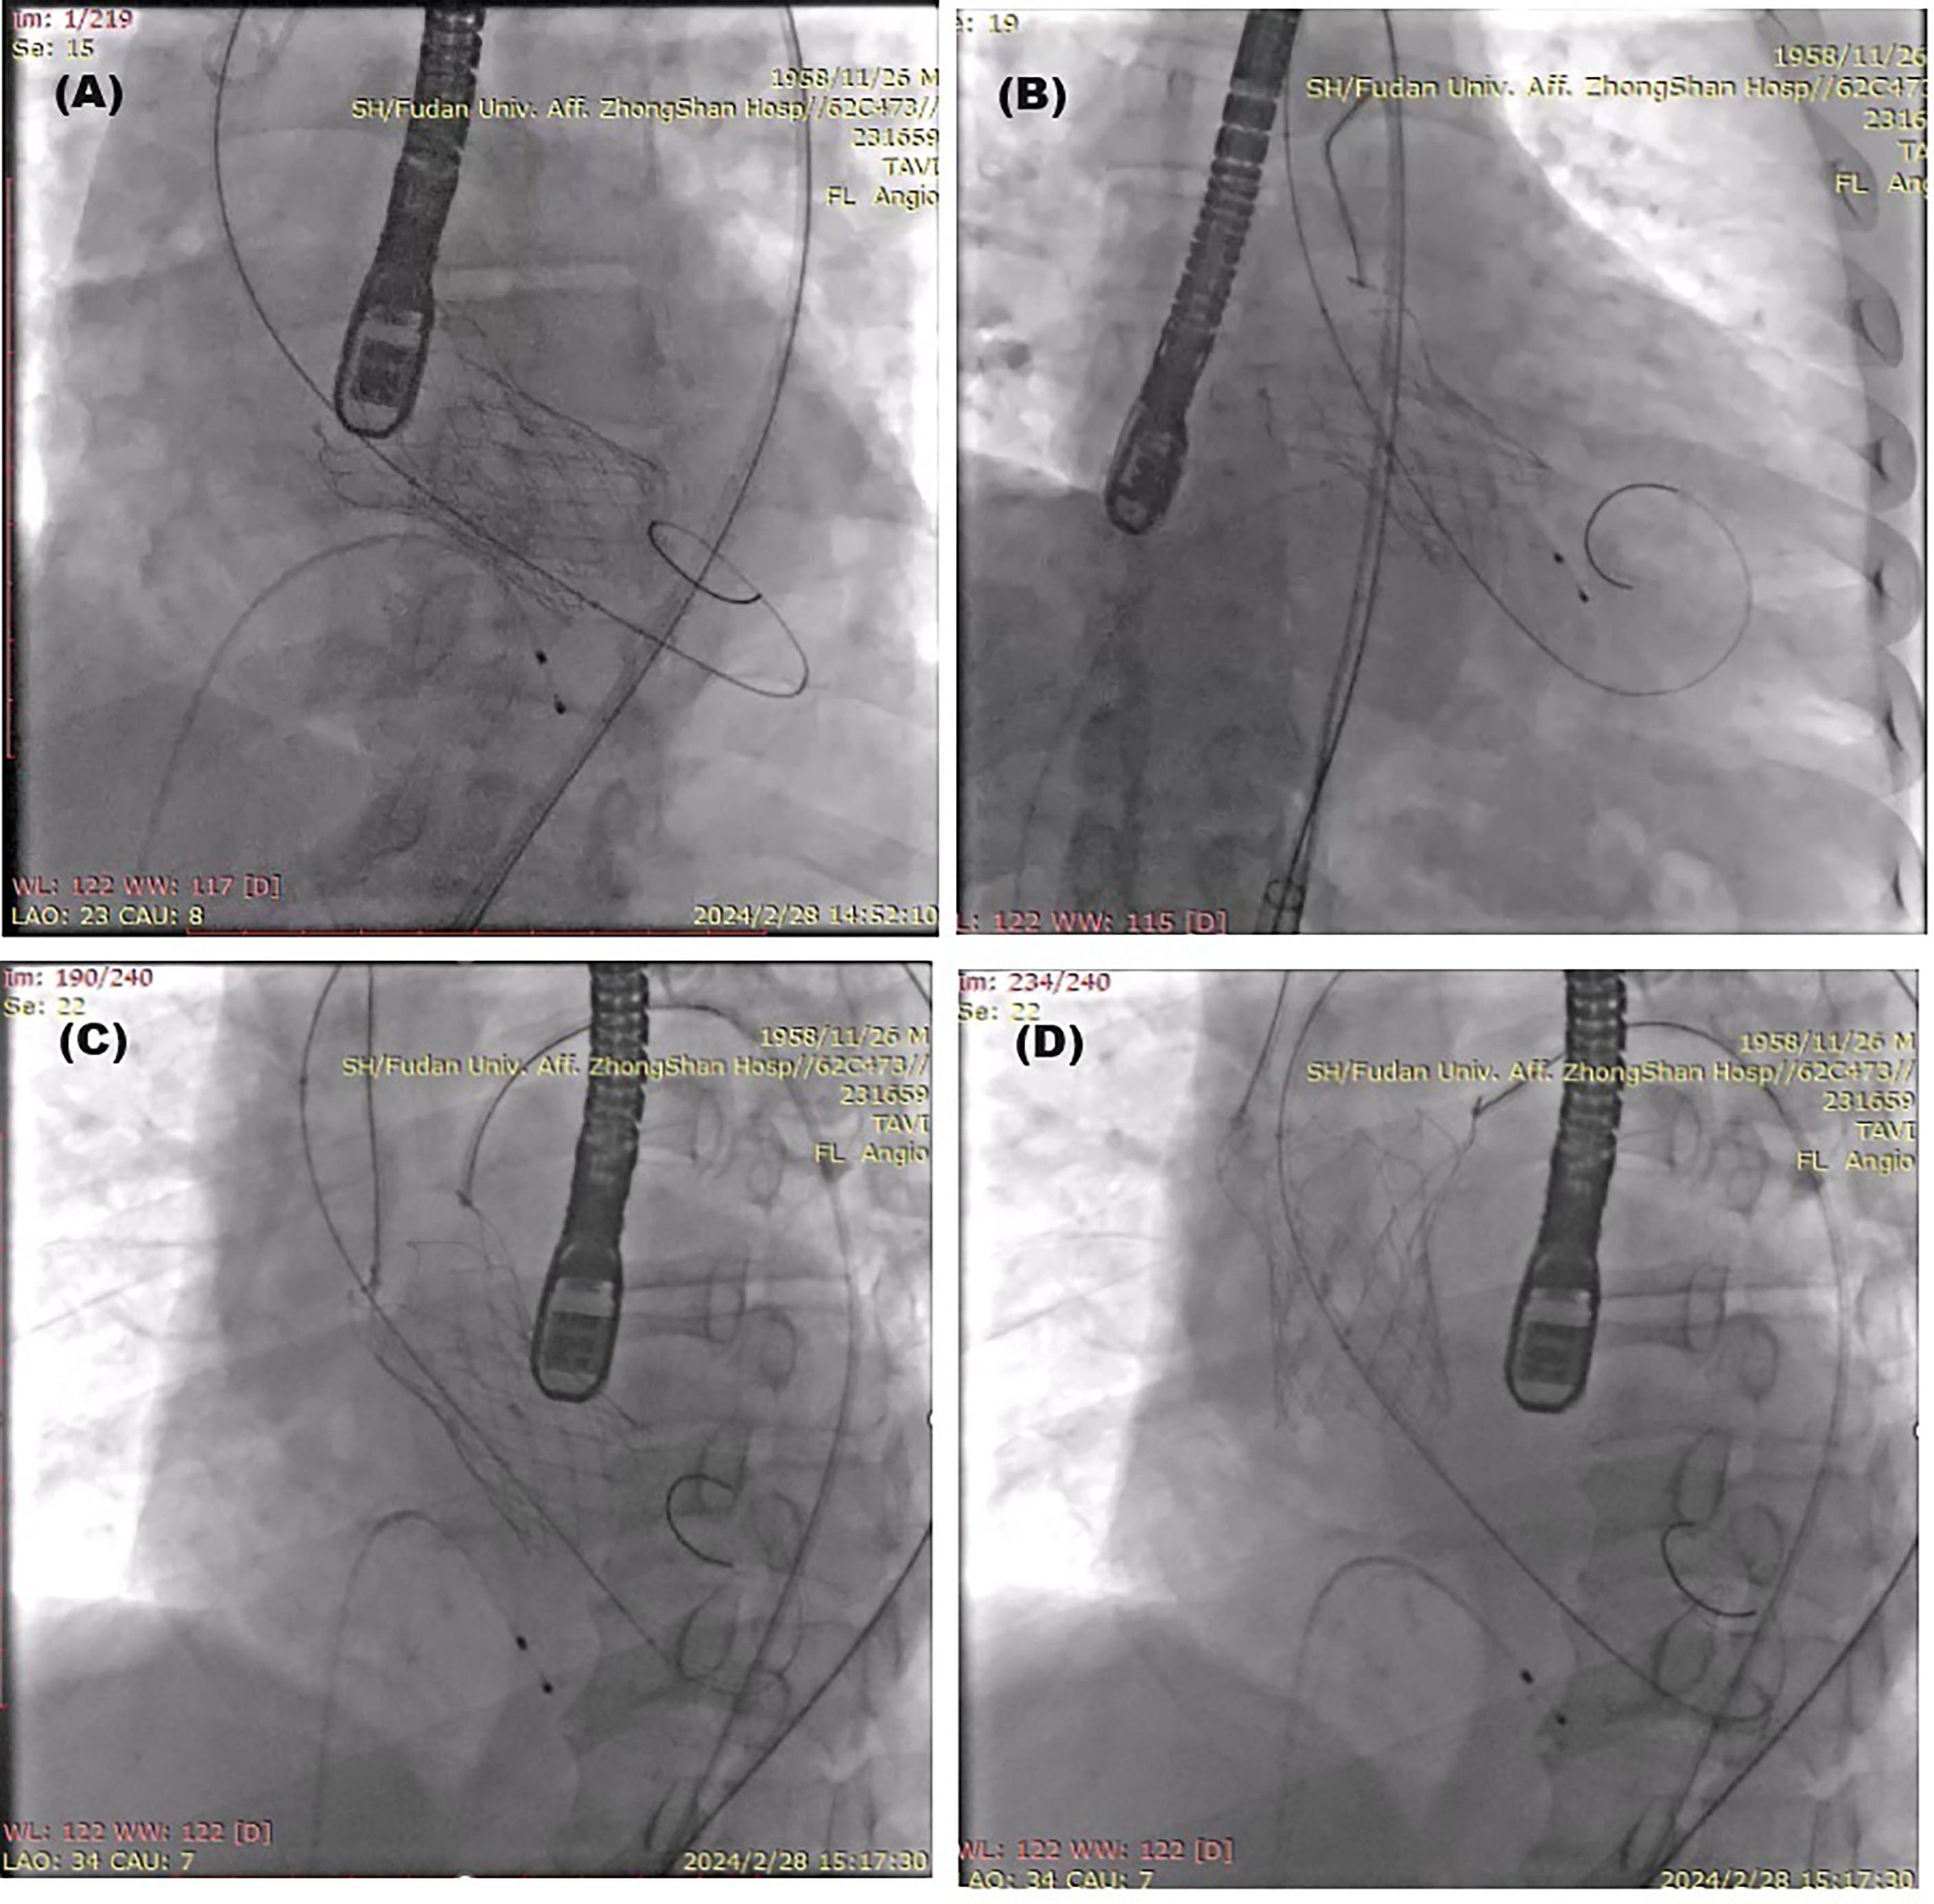

A 30-mm self-expanding VitaFlow valve (MicroPort) was transfemorally delivered and released 1 mm below the annulus plane, but moved downward to the deep left ventricle, affecting the mitral valve function (Figure 2A, Video 1). A snare (Shanghai Shape Memory Alloy Co.) through the transfemoral artery was used to drag the valve upward but failed (Figure 2B) because the unilateral pulling could cause misalignment between the valve and aorta, resulting in increased frictional force when the valve moves upward. A second snare (Shanghai Shape Memory Alloy Co.) was then applied alongside the first snare through the right radial artery to keep the valve and aorta coaxial, and the valve was finally pulled up to the ascending aorta (Figure 2C and D, Video 2).